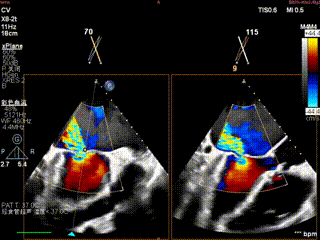

第一枚夹子释放前上彩

第一枚夹子释放后血流